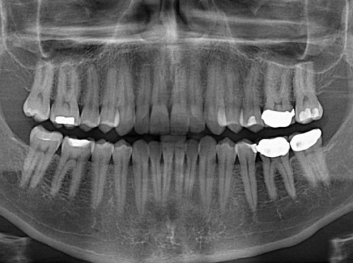

Adam Celiz,是來自諾丁漢大學(xué)的研究人員,他和同事開發(fā)的這種新型合成生物材料,能刺激干細(xì)胞在牙髓部的生長。與普通材料一樣,這種合成材料被填充到牙齒并用UV光硬化。

在體外測試中,材料刺激干細(xì)胞進入牙本質(zhì)的增殖和分化速度,促進形成牙齒骨組織。研究人員認(rèn)為,一旦材料在受損牙齒中應(yīng)用,這些干細(xì)胞可以自動修復(fù)來自填充物上的損壞。在本質(zhì)上,該生物材料將使牙齒自愈。